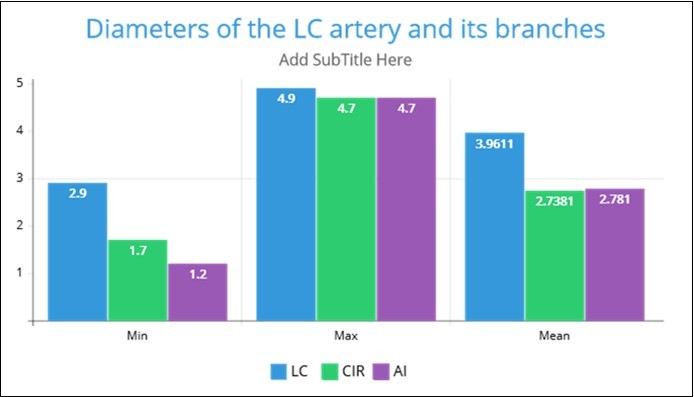

The angiographic measurement of the left coronary (LC) diameter was found in the range between 2.90- 4.90mm, mean 3.96, and Std. Dev. 0.549mm. The left circumflex artery's diameter was found in the range between1.70- 4.70mm, mean 2.73 and Std. Deviation .687mm. The diameter of the anterior interventricular artery was found in the range between 1.20- 4.70mm, mean 2.78, and Std. Deviation .825mm. these diameters are blotted in the Graph 1.

Graph 1.The average diameter of the left coronary (LC) artery, the left circumflex artery (CIR), and anterior interventricular (anterior descending) artery (AI)